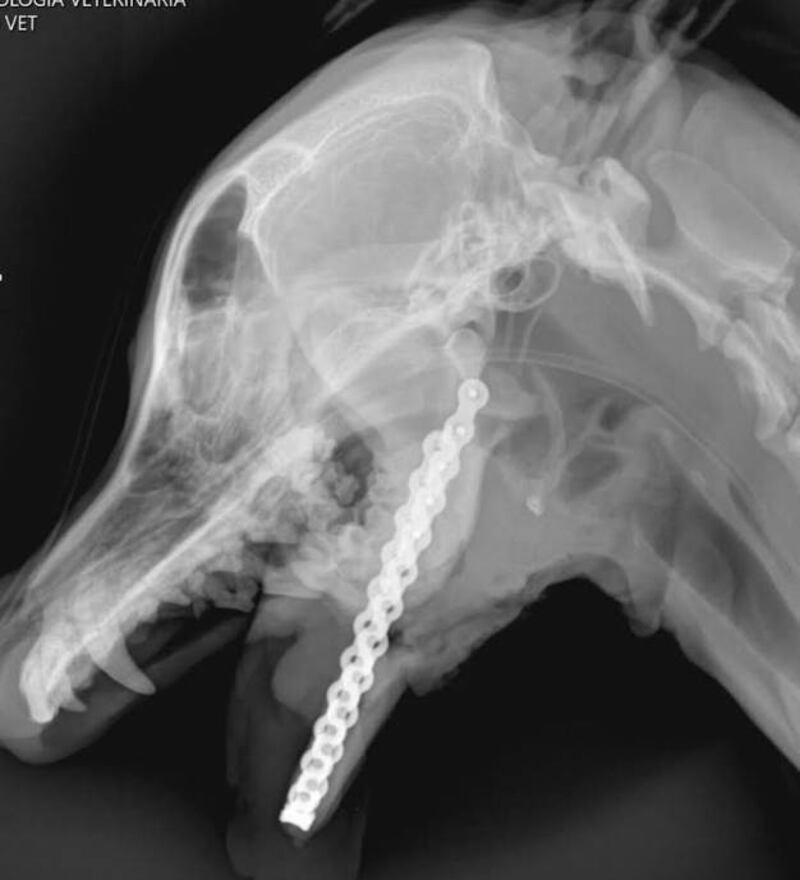

En medio de tanto dolor apareció una luz de esperanza que finalmente se hizo realidad. Tras meses de espera, Canela fue sometida a una delicada cirugía en la que recibió una prótesis de mandíbula diseñada en 3D en el extranjero. La intervención duró varias horas y, por la complejidad del caso, además de ser la primera de este tipo realizada en el país, representó un gran desafío para el equipo médico. A pesar de ello, la operación concluyó con éxito.